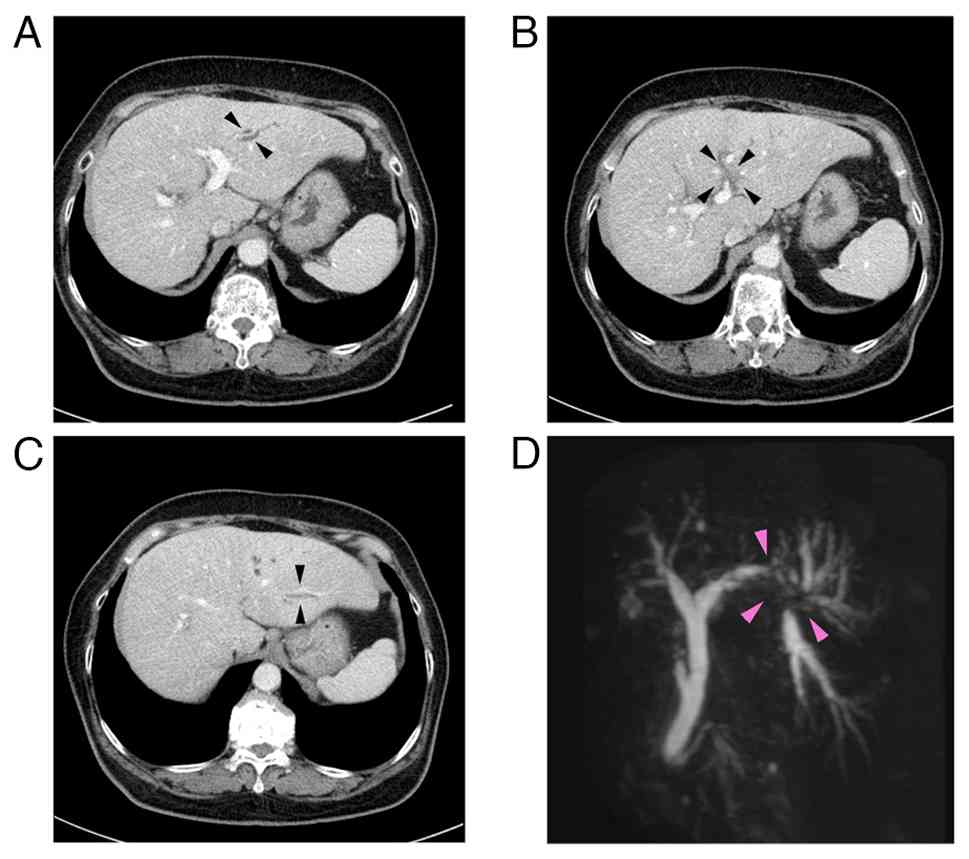

In 2025, a 76-year-old woman, who had been under observation for diabetes and liver dysfunction, was referred to the Department of Gastroenterology, Ota Memorial Hospital, Ota, Japan, due to dilatation of the bile duct and portal vein (P3) obstruction in the left lobe of the liver by contrast-enhanced computed tomography (CECT). Laboratory tests at the first visit were performed at the Department of Clinical Laboratory, Ota Memorial Hospital, as routine testing, and the results were the following: White blood cell count, 7,230/µl (reference range, 3,500-8,500/µl); red blood cell count, 514x104/µl (reference range, 380-520x104/µl); hemoglobin, 15.0 g/dl (reference range, 11.5-15.5 g/dl); platelets, 23.6x104/µl (reference range, 12.0-33.0x104/µl); total bilirubin, 0.74 mg/dl (reference range, 0.4-1.5 mg/dl); aspartate aminotransferase, 32 U/l (reference range, 13-30 U/l); alanine aminotransferase, 27 U/l (reference range, 7-23 U/l); alkaline phosphatase, 200 U/l (reference range, 38-113 U/l); γ-glutamyl transferase, 215 U/l (reference range, 9-32 U/l); HbA1c (NGSP), 6.3% (reference range, 4.6-6.2%); IgG, 1,228 mg/dl (reference range, 861-1,747 mg/dl); carcinoembryonic antigen (CEA), 2.8 ng/ml (reference range, 0.0-5.0 ng/ml); CA19-9, <2.0 U/ml (reference range, 0.0-37.0 U/ml); alpha-fetoprotein, 2.3 ng/ml (reference range, 0.0-10.0 ng/ml); PIVKA-2, 20.47 mAU/ml (reference range, 0.0-39.0 mAU/ml); HBs-Ag (-), HCV-Ab (-), anti-nuclear antibody (-) and anti-mitochondrial antibody (-). A CECT scan revealed an ~1 cm-sized low-density lesion adjacent to the umbilical portion of the left portal vein with peripheral bile duct dilatation in the lateral segment of the liver (Fig. 1A-C). Magnetic resonance cholangiopancreatography revealed the disruption of the bile duct at the bifurcation of B2 and B3 bile ducts (arrows) (Fig. 1D). The ERCP findings demonstrated severe stenosis at the origin of the B3 bile duct, which prevented fine needle aspiration. ENBD tube was placed in the B2 bile duct and serial bile cytology was performed. Samples were prepared with BD SurePathTM liquid-based cytology (SP-LBC) (Becton, Dickinson and Company). In brief, bile juice was centrifuged at 1,400 x g for 5 min at room temperature. The cell pellet was fixed with CytorichTM Red (Becton Dickinson) overnight and then washed. The cells were deposited onto BD SurePathTM Precoated slides (Becton, Dickinson and Company) according to the manufacturer's instructions. Following emersion in 95% ethanol, the slides were subject to Papanicoloau staining with Tissue-Tek Prima® Plus (Sakura Finetek) according to the manufacturer's instructions. The stained glass slides were inspected under a light microscope (BX53; Olympus Corporation).

Imaging studies. (A) CECT in the

portal phase demonstrated the dilatation of the B3 bile duct. (B)

CECT in the portal phase demonstrated a 1x1 cm-sized low density

lesion adjacent to the umbilical portion of the left portal vein.

(C) CECT in the portal phase demonstrated dilatation of the B2 bile

duct. (D) Magnetic resonance cholangiopancreatography revealed

stricture and separation of the left branch of intrahepatic bile

duct at the bifurcation of B2 and B3 bile ducts (arrows). CECT,

contrast-enhanced computed tomography.

Imaging studies. (A) CECT in the portal phase demonstrated the dilatation of the B3 bile duct. (B) CECT in the portal phase demonstrated a 1x1 cm-sized low density lesion adjacent to the umbilical portion of the left portal vein. (C) CECT in the portal phase demonstrated dilatation of the B2 bile duct. (D) Magnetic resonance cholangiopancreatography revealed stricture and separation of the left branch of intrahepatic bile duct at the bifurcation of B2 and B3 bile ducts (arrows). CECT, contrast-enhanced computed tomography.